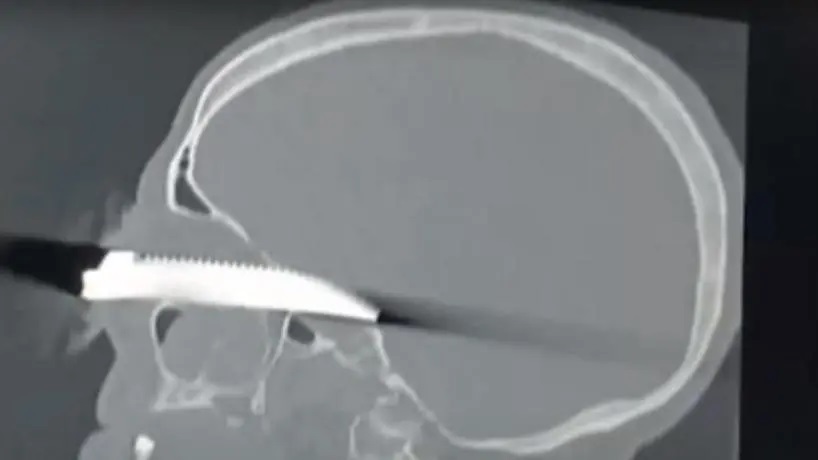

La imagen de los estudios que le realizaron parecen propias de una película de terror. En la radiografía se puede apreciar con claridad la hoja del cuchillo sierrita completamente introducida en el cráneo del paciente que ingresó anoche a la guardia del Hospital Padilla. Se trata de Julio Roberto Sosa, un hombre de 65 años que habría sido atacado por una sobrina.

De acuerdo con el informe policial, el violento suceso ocurrió ayer en el pasaje Exupéry al 2500 y el estado de Sosa, quien será operado en las próximas horas, es grave. “Es una situación grave porque ha penetrado un arma blanca a través del globo ocular y está dentro del cráneo. Ahora se encuentra entubado y en buen estado general”, explicó el director del Hospital Padilla Jorge Valdecantos.

El especialista brindó una serie de recomendaciones acerca de cómo actuar ante lesiones de este tipo: “Nosotros en terminología médica lo llamamos empalamiento porque entró algo dentro del organismo. La recomendación es, si la persona está bien, no tocar. Por ahí, si hay un metal, palo o algo que entra en el abdomen o en el tórax no hay que retirarlo, hay que traerlo como está a la guardia. Hay que venir urgente a la guardia y no sacar”.

“Se han dado casos de estas heridas penetrantes en órganos vitales como arterias o venas que hay que dejarlos donde están porque, si uno las retira, empieza el sangrado y ahí perdemos al paciente como consecuencia del sangrado”, explicó Valdecantos.